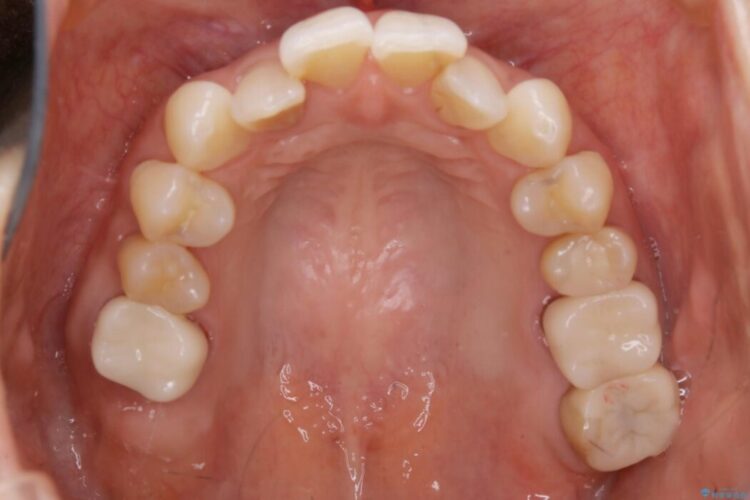

歯列弓全体の形状を整えるとともに歯の大きさもコントロールすることで非抜歯にて矯正を行いました。

気になっていたガタつきも改善され、患者様にはご満足いただけました。